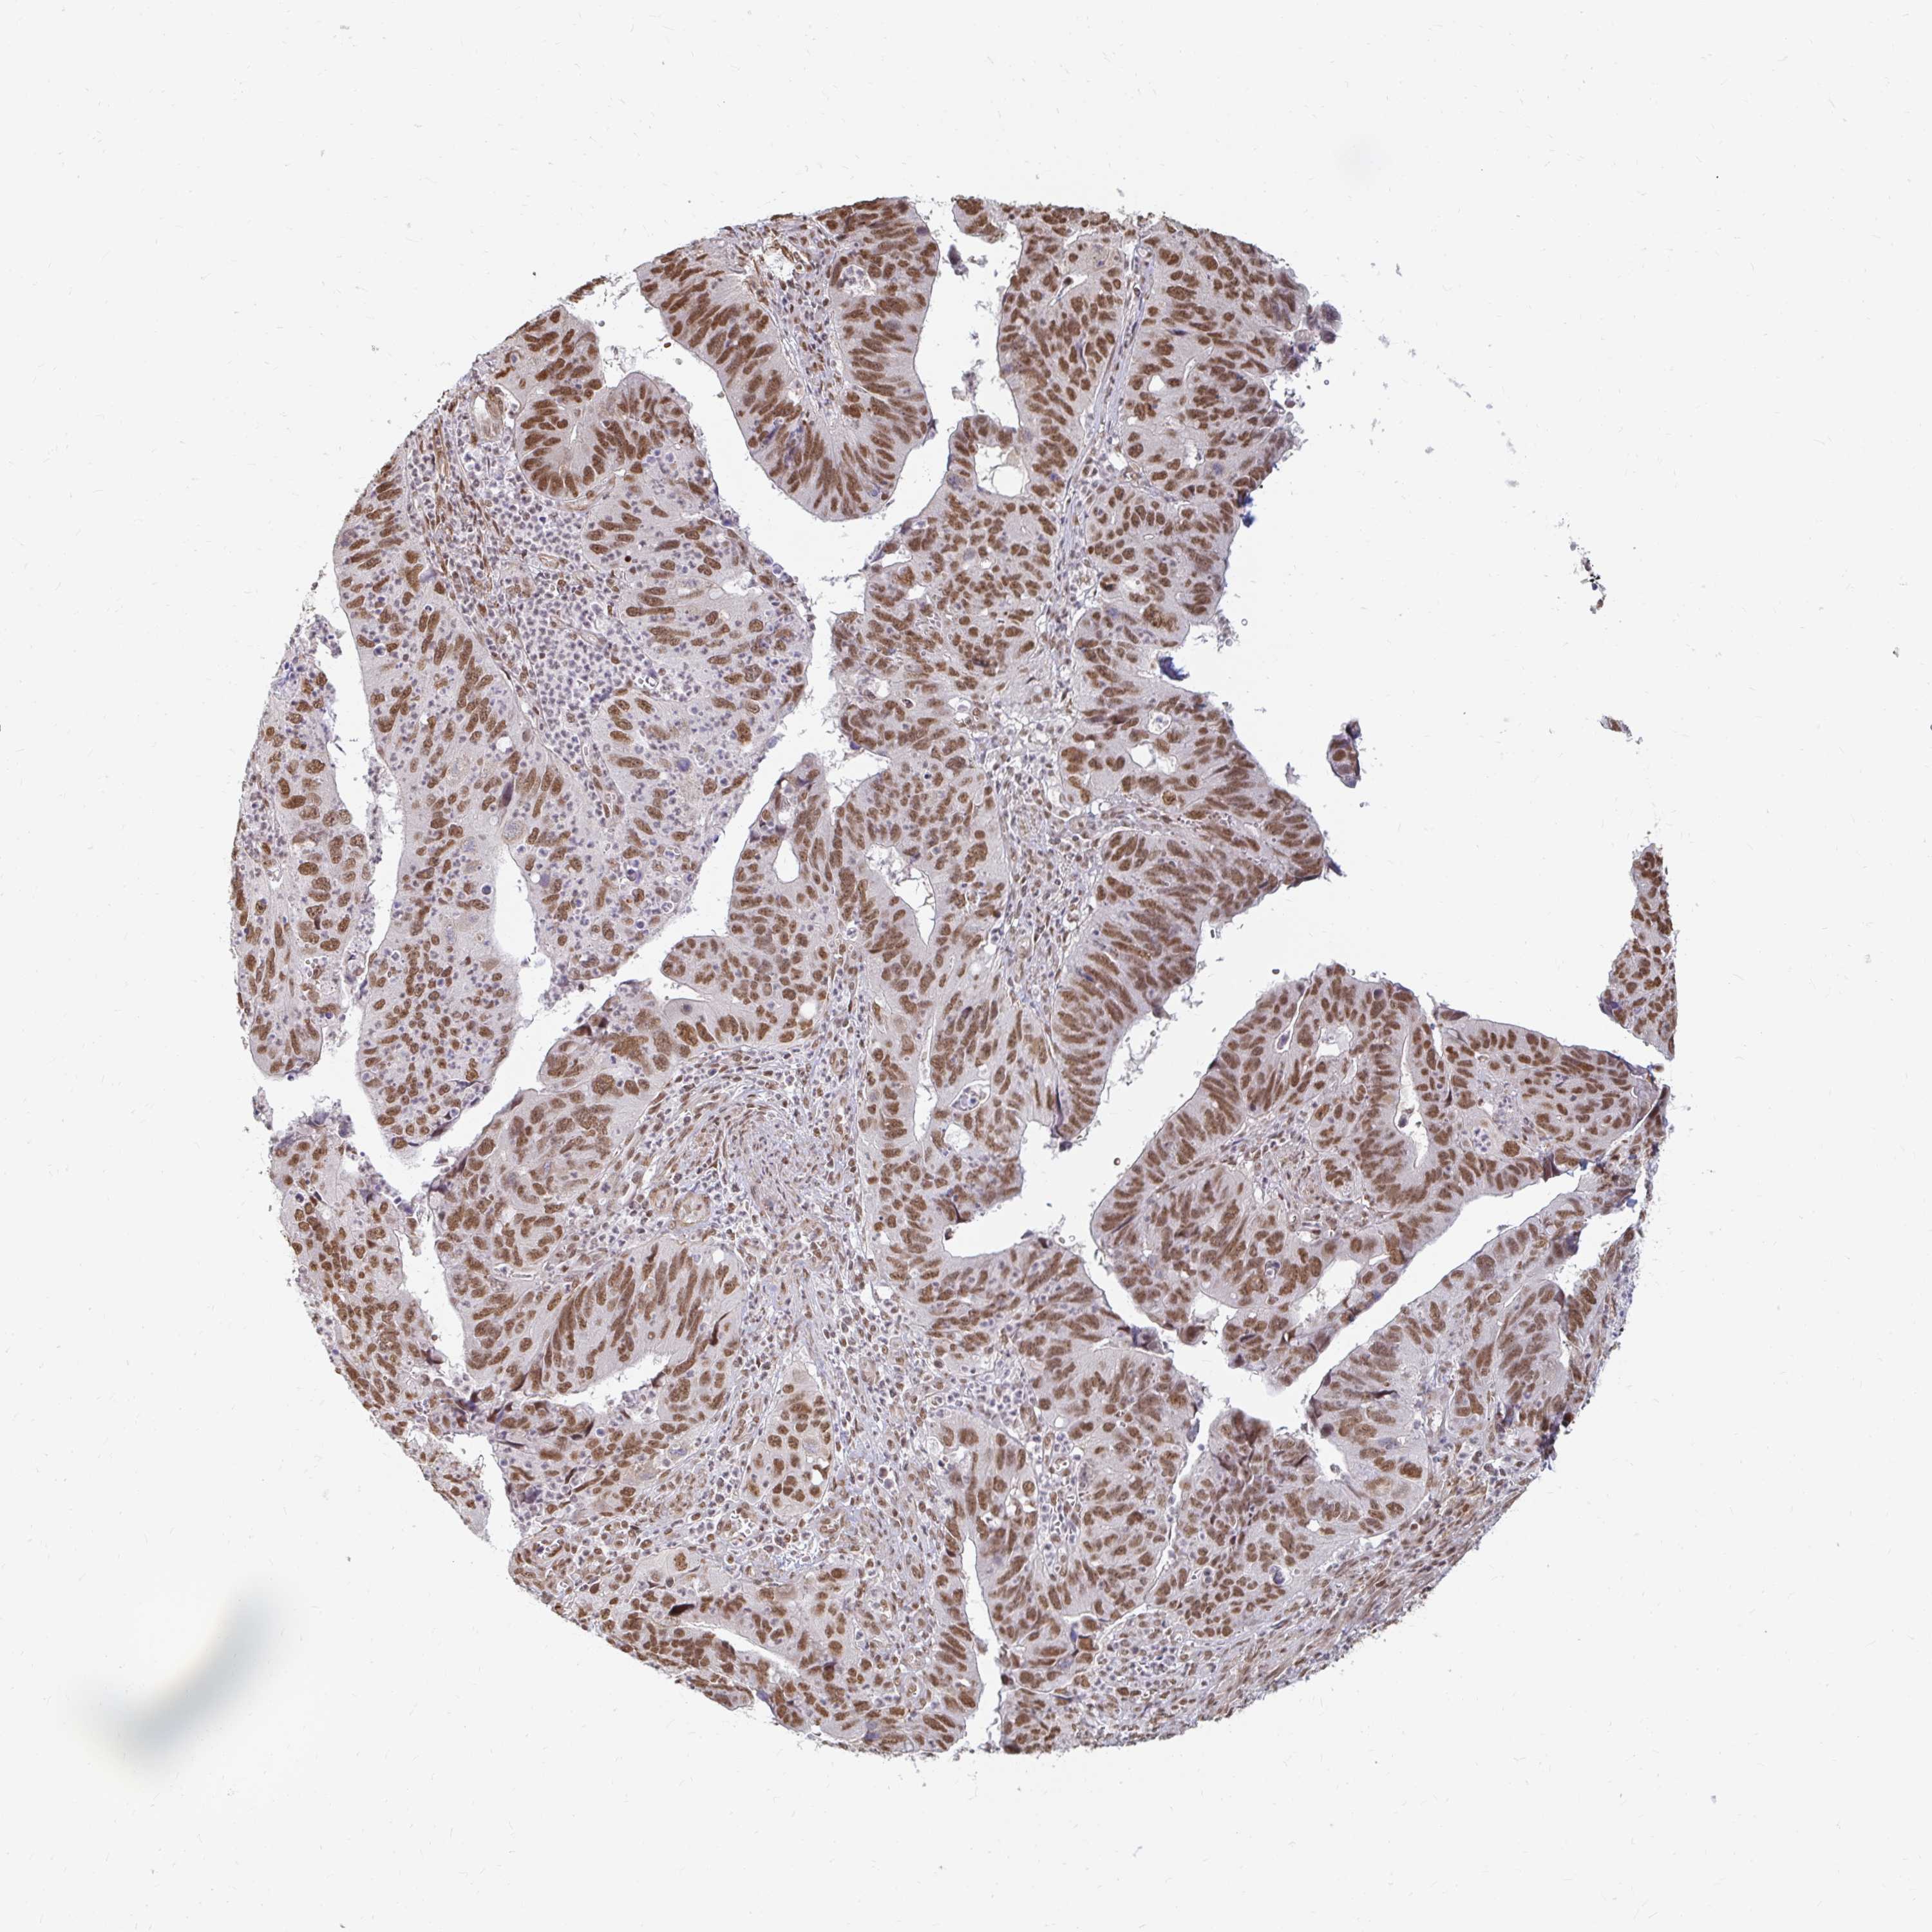

STOMACH CANCER - Protein expressioni

A mouse-over function shows sample information and annotation data. Click on an image to view it in a full screen mode. Samples can be filtered based on level of antibody staining by selecting one or several of the following categories: high, medium, low and not detected. The assay and annotation is described here.

Note that samples used for immunohistochemistry by the Human Protein Atlas do not correspond to samples in the TCGA dataset.

Antibody stainingi

Antibody staining in the annotated cell types in the current human tissue is reported as not detected, low, medium, or high, based on conventional immunohistochemistry profiling in selected tissues. This score is based on the combination of the staining intensity and fraction of stained cells.

Each image is clickable and will lead to virtual microscopy that enables deeper exploration of all samples and also displays staining intensity scores, fraction scores and subcellular localization as well as patient and tissue information for each sample.

Antibody HPA041057

Antibody HPA058707

Antibody CAB011532

Staining

High

Medium

Low

Not detected

Intensity

Strong

Moderate

Weak

Negative

Quantity

>75%

75%-25%

<25%

None

Location

Nuclear

Cytoplasmic/membranous

Cytoplasmic/membranous,nuclear

Adenocarcinoma, NOS

Adenocarcinoma, High grade